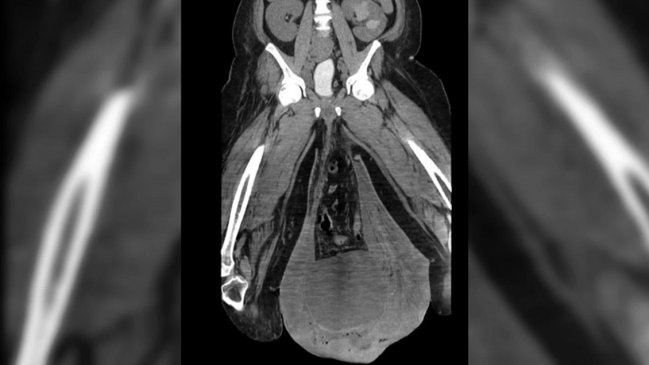

Un hombre de 43 años fue víctima de un extraño caso médico en que sus testículos se hincharon al punto de quedar del tamaño de pelotas de fútbol o de básquetbol.

El hombre había sido hospitalizado con fiebre y dolores cuando reveló su preocupante hinchazón: su escroto pesaba más de 3 kilos y le impedía hacer cualquier cosa con normalidad.